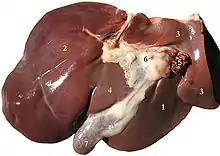

Structure

The liver is a dark reddish brown, wedge-shaped organ with two lobes of unequal size and shape. A human liver normally weighs approximately 1.5 kilograms (3.3 pounds)[9] and has a width of about 15 centimetres (6 inches).[10] There is considerable size variation between individuals, with the standard reference range for men being 970–1,860 grams (2.14–4.10 lb)[11] and for women 600–1,770 g (1.32–3.90 lb).[12] It is both the heaviest internal organ and the largest gland in the human body. It is located in the right upper quadrant of the abdominal cavity, resting just below the diaphragm, to the right of the stomach, and overlying the gallbladder.[5]

Lobes

The liver is grossly divided into two parts when viewed from above – a right and a left lobe – and four parts when viewed from below (left, right, caudate, and quadrate lobes).[14]

The falciform ligament makes a superficial division of the liver into a left and right lobe. From below, the two additional lobes are located between the right and left lobes, one in front of the other. A line can be imagined running from the left of the vena cava and all the way forward to divide the liver and gallbladder into two halves.[15] This line is called Cantlie's line.[16]

Other anatomical landmarks include the ligamentum venosum and the round ligament of the liver, which further divide the left side of the liver in two sections. An important anatomical landmark, the porta hepatis, divides this left portion into four segments, which can be numbered starting at the caudate lobe as I in an anticlockwise manner. From this parietal view, seven segments can be seen, because the eighth segment is only visible in the visceral view.[17]